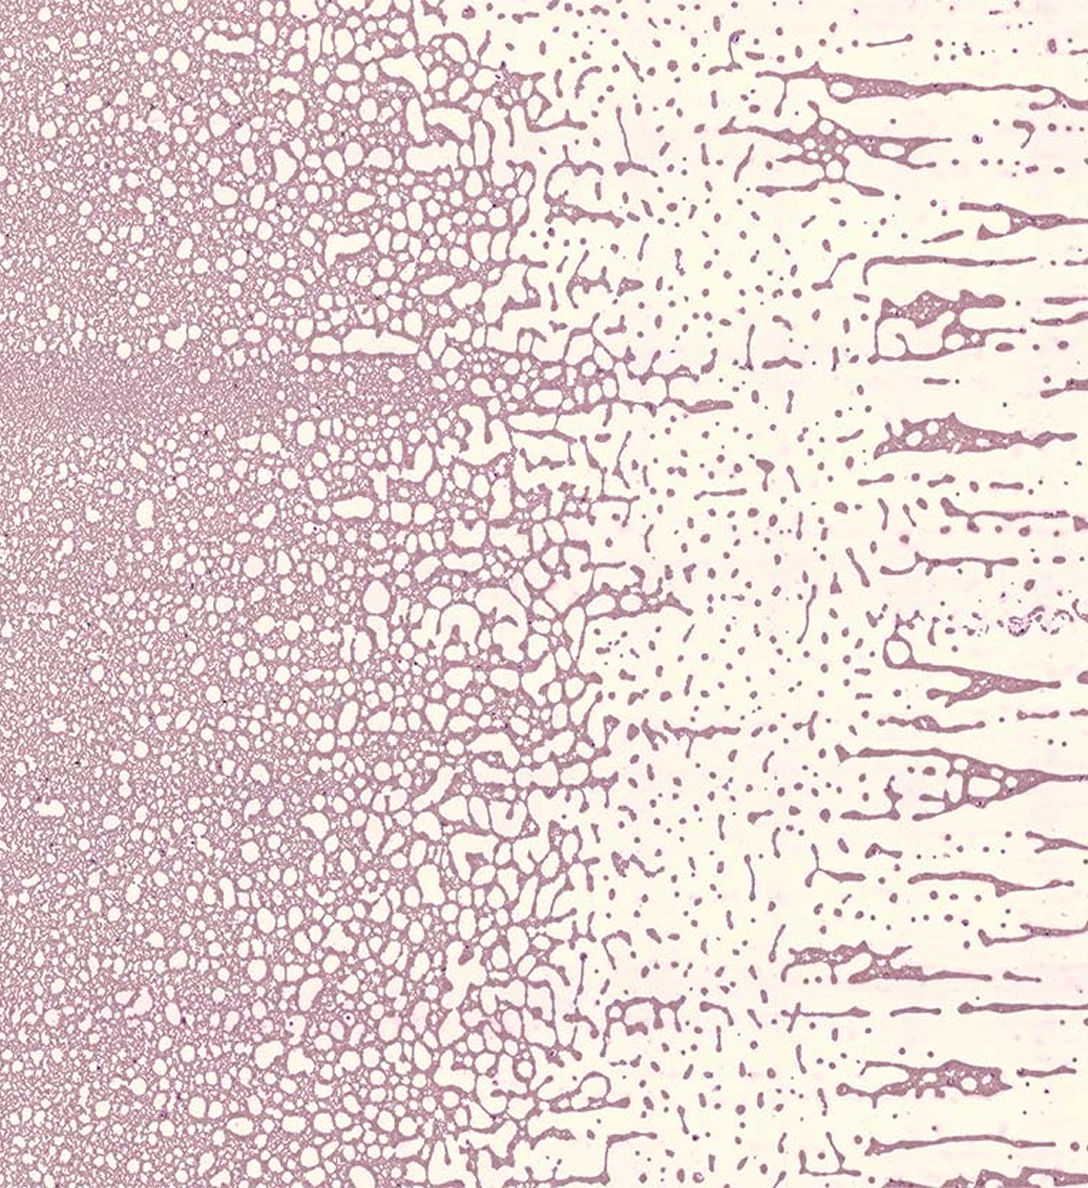

Capture digitalmente todas las áreas clínicamente relevantes a 100x, incluyendo el borde de la extensión (feathered edge), y navegue dinámicamente desde la vista completa de la muestra hasta células individuales.

La IA analiza más de 10,000 glóbulos rojos en 1,000 campos de visión, pre-calificando 22 parámetros morfológicos con detección de esquistocitos y otras morfologías clínicamente significativas.

Las imágenes de las láminas completas le permiten navegar desde el contexto total de la muestra hasta células individuales con resolución de inmersión en aceite de 100x, ya sea que esté en el laboratorio o a kilómetros de distancia.*

Explore muestras reales de sangre periférica y médula ósea. Haga zoom, aleje la imagen y explore el contexto completo. Experimente la diferencia Full-Field.